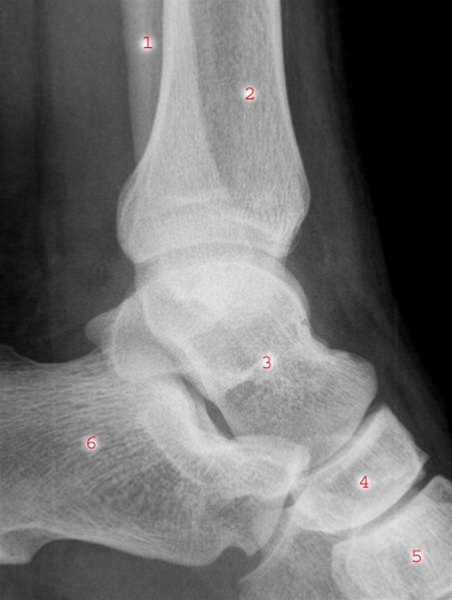

Ankelbillede set fra lateralsiden

1. Fibula (lægbenet)

2. Tibia (skinnebenet)

3. Talus (rullebenet eller springbenet)

4. Os naviculare (bådbenet)

5. Os cuneiforme (kilebenet)

6. Calcaneus (hælbenet)